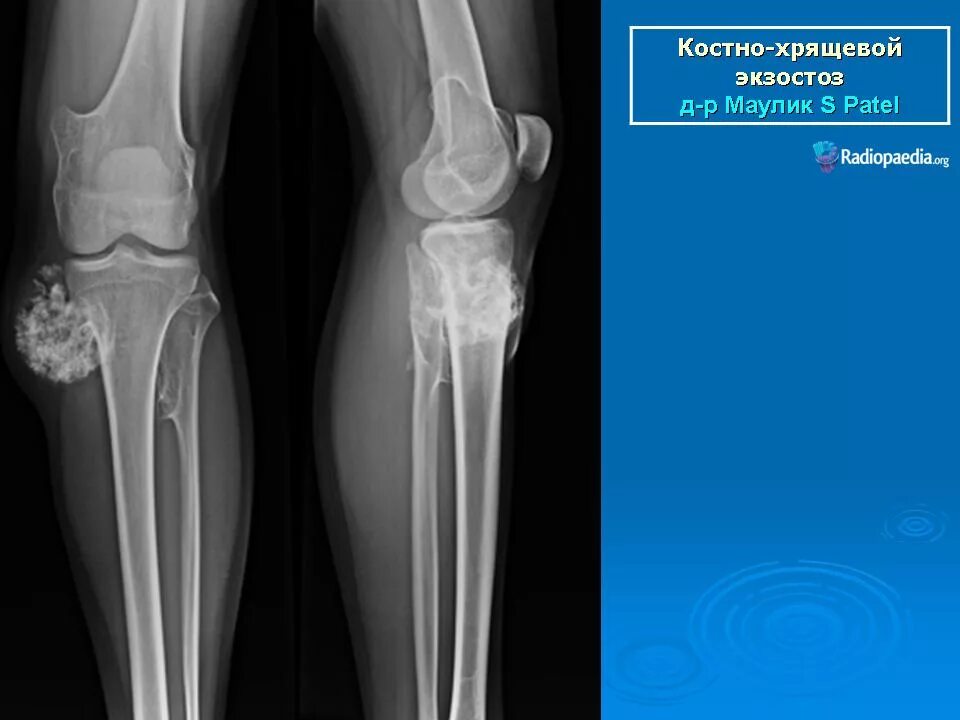

Экзостоз мкб 10